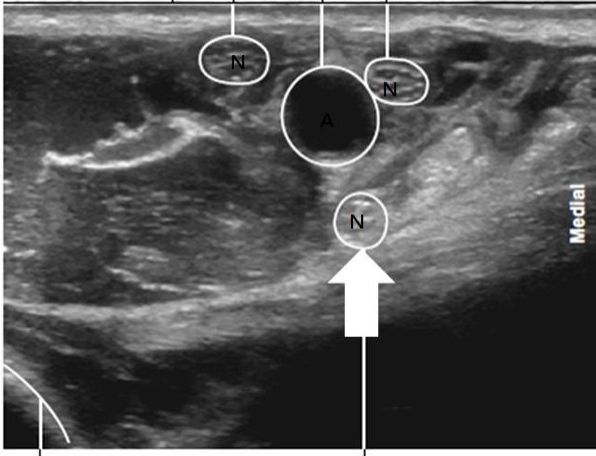

71 圖中為經靜脈給予Rocuronium 1.2mg/kg後以Train-of-four(TOF)監測神經肌肉傳導之恢復情況,完全阻斷神 經肌肉傳導後3分鐘,再經靜脈投予箭號所指藥物,請問最可能是何種藥物與劑量?